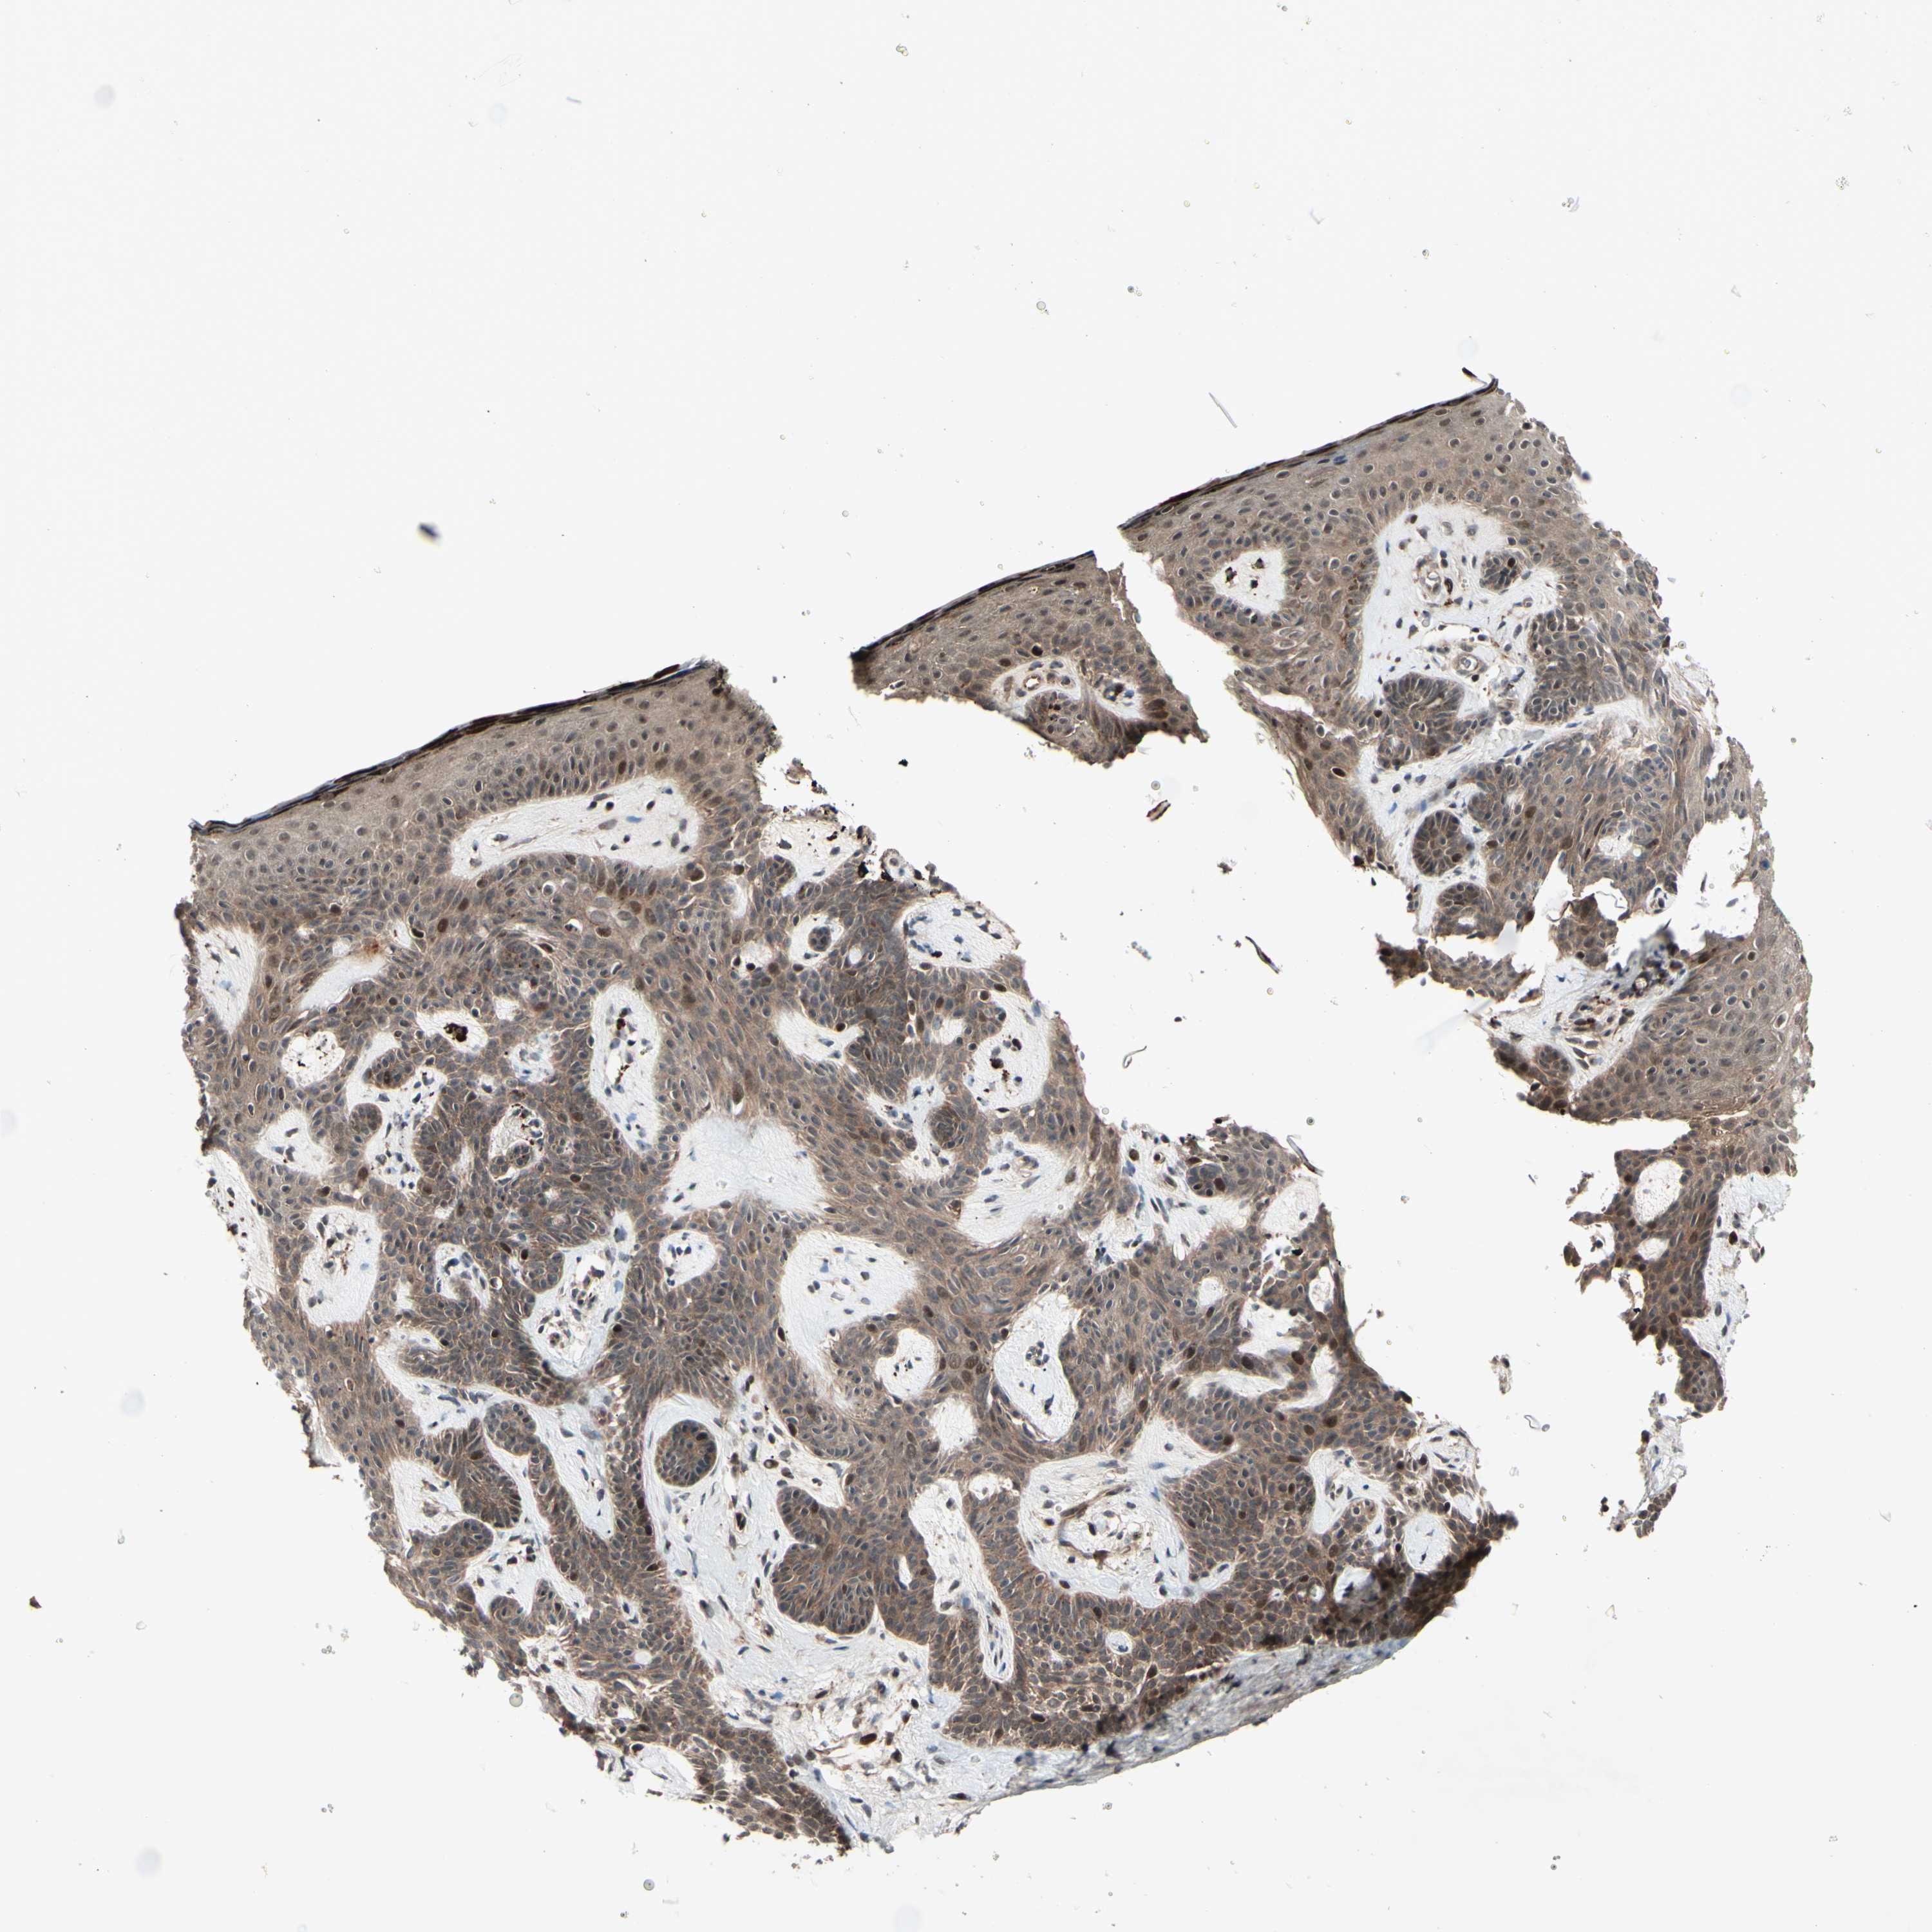

SKIN CANCER - Protein expressioni

A mouse-over function shows sample information and annotation data. Click on an image to view it in a full screen mode. Samples can be filtered based on level of antibody staining by selecting one or several of the following categories: high, medium, low and not detected. The assay and annotation is described here.

Antibody stainingi

Antibody staining in the annotated cell types in the current human tissue is reported as not detected, low, medium, or high, based on conventional immunohistochemistry profiling in selected tissues. This score is based on the combination of the staining intensity and fraction of stained cells.

Each image is clickable and will lead to virtual microscopy that enables deeper exploration of all samples and also displays staining intensity scores, fraction scores and subcellular localization as well as patient and tissue information for each sample.

Antibody HPA010811

Staining

High

Intensity

Quantity

Location

Squamous cell carcinoma, NOS

Squamous cell carcinoma, metastatic, NOS